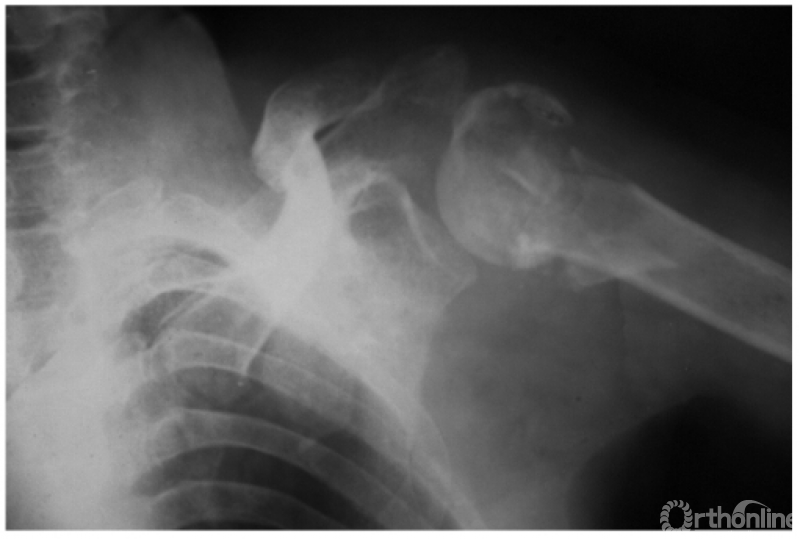

肩关节后脱位是所有大关节脱位中最易误诊的一种损伤,其误诊率可高达60%,因此该病有“诊断的陷阱”之称,有学者指出肱骨头关节面与盂前缘距离大于6mm时应高度怀疑有后脱位的可能。

此外,由于脱位后上臂外旋受限,因此即使在最大外旋位拍片时仍不能显示出肱骨颈及大结节的轮廓。例:肱骨头离开关节盂而向后外上方(肩峰之下)移位且内旋,致肱骨头与肱骨干在一直线上,招致肩肱曲线不流畅,肱骨头关节面与盂前缘距离大于6mm并小结节骨折(如下图)。